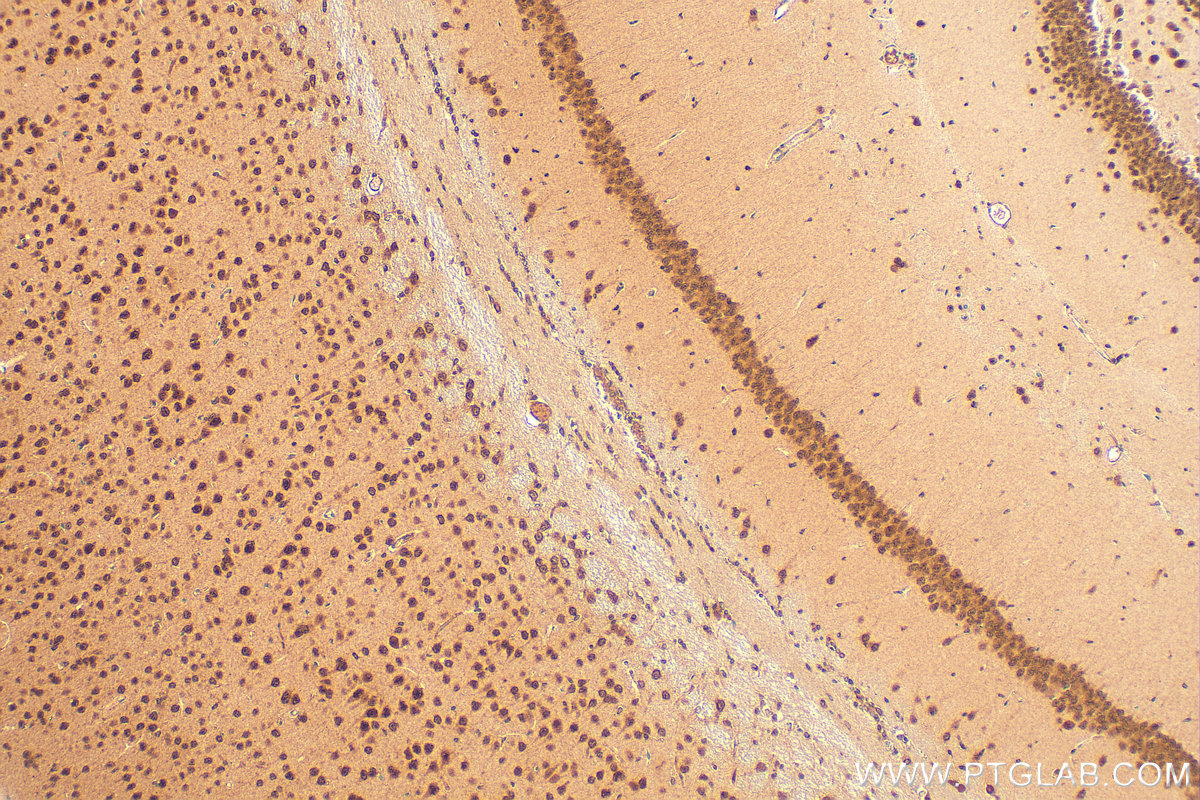

| Positive IHC detected in | mouse brain tissue Note: suggested antigen retrieval with TE buffer pH 9.0; (*) Alternatively, antigen retrieval may be performed with citrate buffer pH 6.0 |

| Immunohistochemistry (IHC) | IHC : 1:200-1:1000 |